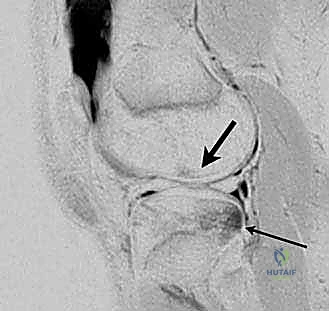

شكل 1: صورة رنين مغناطيسي سهمي تُظهر نمط الكدمة العظمية المميزة لإصابة الرباط الصليبي الأمامي الحادة (سهم رفيع). لاحظ زيادة الإشارة على الجانب الخلفي من الهضبة الظنبوبية الجانبية والجانب البعيد من عظم الفخذ عند الثلمة النهائية.

2. الرنين المغناطيسي (MRI): هو المعيار الذهبي. لا يُظهر فقط القطع في الرباط، بل يكشف عن الإصابات المصاحبة في الغضاريف الهلالية والأربطة الأخرى.

شكل 2: صورة رنين مغناطيسي سهمي عبر الجانب الجانبي للركبة، تُظهر نمط الكدمة العظمية المميزة لإصابة الرباط الصليبي الأمامي الحادة (سهم رفيع). هذه الكدمات تعكس الصدمة التي تحدث عندما يندفع عظم الساق إلى الأمام على عظم الفخذ.